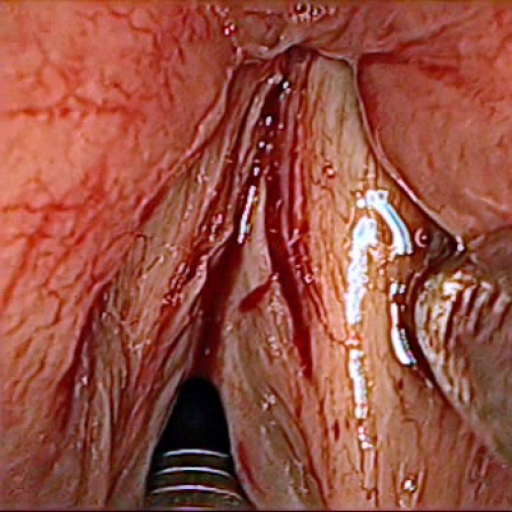

All subsequently described models are trained and evaluated on a dataset, containing 536 manually segmented in vivo color images of the larynx during two different resection surgeries with a resolution of pixels. The images have been captured with a stereo endoscope (VSii, Visionsense, Petach-Tikva, Israel) in an in vivo laryngeal surgery and have been used in prior studies schoob2016 . They are categorized in the 7 different classes void, vocal folds, other tissue, glottal space, pathology, surgical tool and intubation with indices {0, 1, 2, 3, 4, 5, 6}, respectively, which is represented by the gray values of the label maps (see Fig 1). The dataset consists of 5 different sequences from two patients (named SEQ1–4 from patient 1 and SEQ5–8 from patient 2). The sequences have following characteristics:

Figure 4 visualizes class label predictions for selected example images from the test set after training on the augmented dataset. As expected from the IoU values, the prediction of SegNet has major errors in classes pathology, vocal folds and other tissue. The results of UNet are better in general, but it provided visible errors on the edges of two adjacent areas. ENet and ErfNet both achieved good results, with ErfNet also resolving edges and smaller areas well. When zooming into the label maps, it is visible that ENet has a strong aliasing effect on the edges, whereas ErfNet results in smoother edges. The ensemble results are reported for ErfNet+UNet configuration, which provided overall best results. Please see the supplemental video material associated with this publication.

The prediction uncertainties in Fig. 4 give an estimate on how confident the model is for a specific pixel of the selected images. UNet and SegNet use normal dropout for stochastic inference, whereas ENet and ErfNet use spatial dropout (turning off full feature maps). In contrast to normal dropout, there is currently no proof of spatial dropout acting as Bayesian approximation gal2016 . This must be taken into account when considering the uncertainty maps. It is worth mentioning that ENet and ErfNet have a higher uncertainty in general and especially on other tissue. A possible explanation for this could be the low numbers of parameters having less redundancies compared to UNet and SegNet (see Tab. 2). Furthermore, it can be observed that with the exception of ErfNet, all models show a high uncertainty for pathology. On the other hand, all models show low uncertainties for vocal folds, which can be interpreted as good generalization for this class.